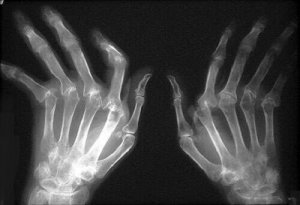

Niveltulehdus on melko yleinen sairaus etenkin naisilla. Sen aiheuttaa tulehdus yhdessä tai useammassa nivelessä, ja siihen liittyy usein myös ruston heikkeneminen. Niveltulehdus on kivulias ja vaikuttaa suoraan elämänlaatuun. Tässä voit oppia muutaman tavan vähentää niveltulehduksen riskiä ja lievittää sen oireita.

Asiantuntijoiden mukaan niveltulehduksia on olemassa yli sata erilaista tyyppiä. Kaksi niistä on tavallisimpia: nivelrikko ja nivelreuma. Molemmat ovat kivuliaita sairauksia, jotka aiheuttavat paljon kärsimystä, tulehduksia, punaisuutta ja jäykkyyttä – oireita, joista voi helposti tulla kroonisia.

Äkillinen turvotus on tavanomaista, esimerkiksi sormien puutuminen, tulehtuminen ja muuttuminen punaisiksi. Älä jätä tätä huomioimatta. Mitä nopeammin alat hoitaa niveltulehdusta, sen parempi.